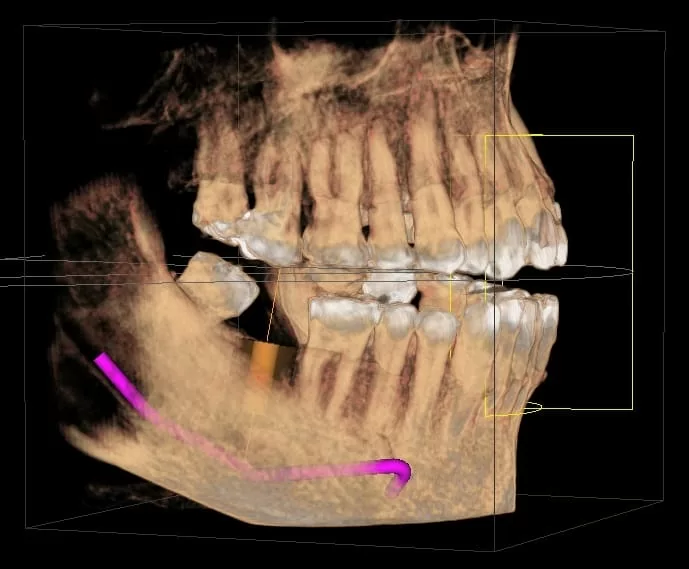

- 拍攝3D電腦斷層,進行植牙評估。<圖一>

斷層掃描-植體.神經管…模擬 <圖一>